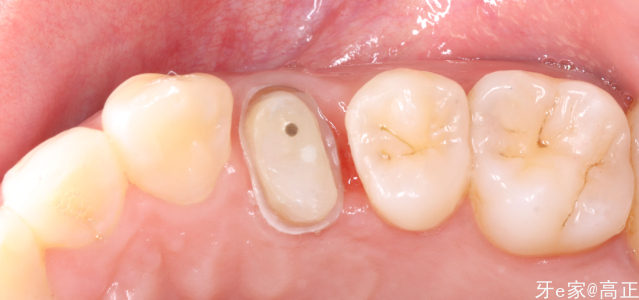

去腐,放置橡皮障隔离

放置豆瓣成型片,髓腔内放置特氟龙隔离

检查边缘是否密合,不密合的位置可以放置特氟龙挤压

树脂制备假壁

颊舌侧各放置一枚纤维桩,基牙预备

聚合瓷全冠